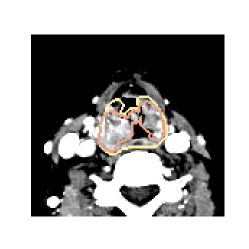

The ground truth segmentation masks were defined as the union of the oncologist delineated GTV and pathologic lymph nodes. Images were cropped to reduce their size whilst retaining a sufficiently large region of interest (ROI) of the head and neck region (see \figurereffig:results). The network was trained on transversal image slices.

fig:results shows the oncologist ground truth delineations and the CNN predicted segmentations superimposed on input images, for a case with moderate CNN performance (Dice coefficient in the range 0.65-0.72).